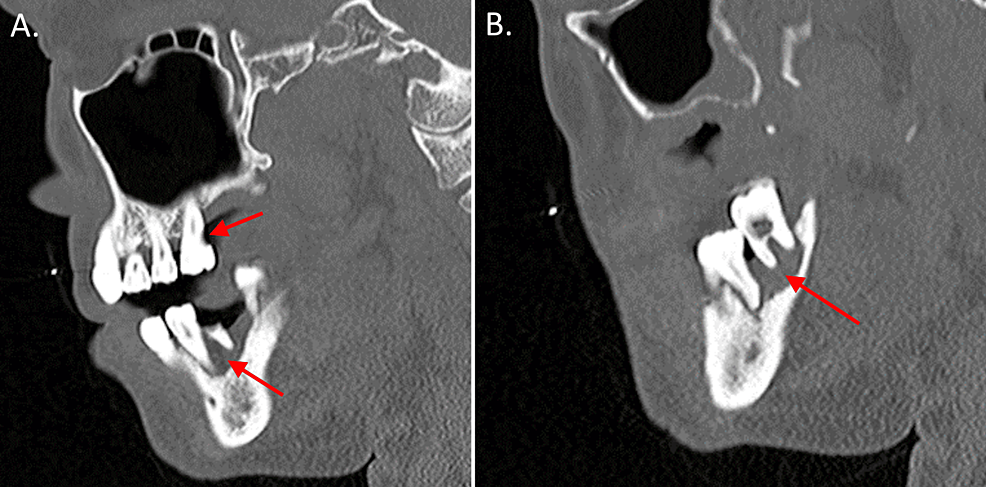

CBCT images (a, b) of the cross section of the plane of the protostylid in tooth #26. (c) The vertebral plane of the protostylid in tooth #26. (d) A 3D reconstruction of the protostylid in tooth #26. Red solid arrows indicate the protostylid.